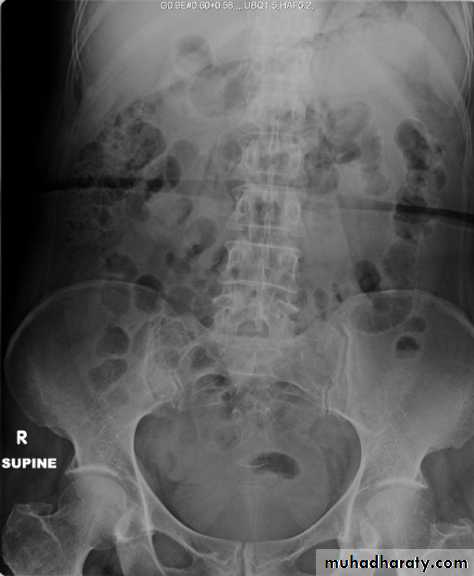

X-Ray: KUB (kidneys, ureters, bladder)

A plain radiograph of the abdomen and pelvis includes the area above both adrenal glands (lower chest) and extends to 2 cm below the symphysis pubis(includes the external genitalia)site, sex, stones, psoas shadow, skeleton, and soft tissue shadow.